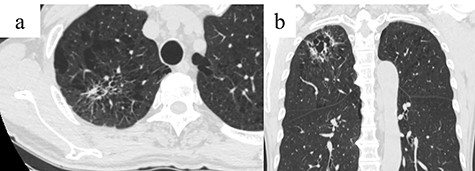

A 66-year-old man with a history of diabetes mellitus and atrial fibrillation visited our hospital after a routine health screening when an abnormality was detected on chest computed tomography (CT). His physical examination was unremarkable. A tumor biomarker test revealed elevated carcinoembryonic antigen (7.3 ng/ml) levels; all other biochemical markers were within normal limits. The chest CT revealed an irregular emphysematous cyst and an infiltrative shadow, 60 mm in diameter, along the cyst wall in the right upper lobe (Fig. 1a and b). The hilar or mediastinal lymph nodes were not swollen. We made a preoperative diagnosis of suspected primary lung cancer (cT3N0M0, stage IIB) and performed right upper lobectomy with hilar and mediastinal lymph-node dissection by video-assisted thoracic surgery. Intraoperatively, the mediastinal pleura was incised in the right superior mediastinal dissection using an energy device, and the anterior surface of the trachea was dissected with clipping, as appropriate. Retrospectively, a tortuous duct was detected near the cranial side in the superior mediastinal dissection area, which was dissected using the energy device (Fig. 2). From the histological findings, lung adenocarcinoma (pT1cN0M0, stageIA3) was diagnosed. On postoperative day (POD) 1, milky fluid was drained after the patient resumed eating. The triglyceride level in the pleural fluid was elevated to 457 mg/dl, and the patient was diagnosed with chylothorax. A low-fat diet (fat intake 35 g/day) was administered to the patient, but 500-ml fluid drainage was observed in 24 h. A revision surgery was performed on POD 2, 3 h after intake of 10-g butter and 200-ml milk. A disconnected duct was observed in the cranial side of the right superior mediastinal dissection area from which the chyle leakage originated. The disconnected duct coursed from the anterior mediastinum to the ventral side of the superior vena cava. This was suggested as the main trunk of the thoracic duct flowing into the right venous angle and the cause of the chylothorax. The thoracic duct could not be identified in the right posterior mediastinum; therefore, the thoracic duct was clipped in the right superior mediastinal dissection area (Supplementary Video 1). After reoperation, no chyle leakage occurred, and the patient’s postoperative course was uneventful. At 18 months postoperatively, there was no recurrence of either lung cancer or chylothorax. The patient provided informed consent for publication of this case report.

Chest CT showing an infiltrative shadow along the cyst wall with an irregular emphysematous cyst in the right upper lobe (arrow); (a) Axial view and (b) coronal view.